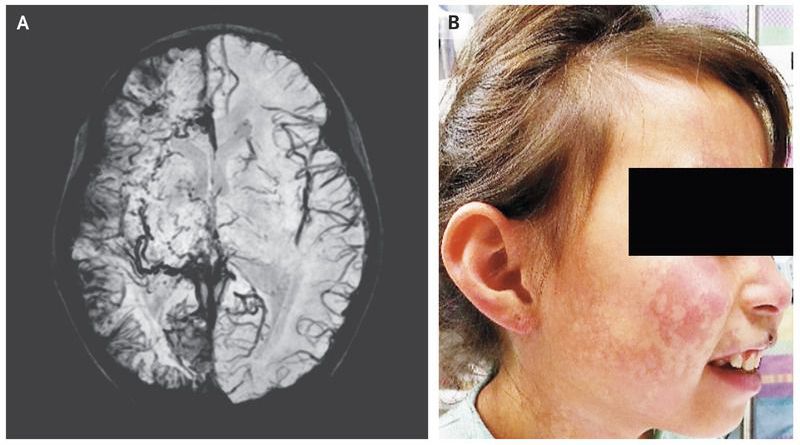

A 6-year-old girl was brought to the emergency department after the sudden onset of weakness in the left arm and leg. She also reported a 2-day history of pain in her right eye. No seizure activity had been witnessed. She had a nonpalpable red lesion on the right side of her face, and the intraocular pressure was elevated in both eyes. Magnetic resonance imaging (MRI) of the head revealed right cerebral atrophy with leptomeningeal enhancement along the right cerebral convexity. Susceptibility-weighted MRI (Panel A) revealed abnormal leptomeningeal capillary vessels along the right cerebral convexity. The MRI and clinical findings were consistent with the Sturge–Weber syndrome, a rare congenital vascular disorder characterized by a cutaneous capillary malformation, also called port-wine birthmark (Panel B shows the patient’s face 2 years after the initial presentation), and abnormal capillary venous vessels in the brain and eye that can lead to glaucoma, seizures, stroke, and intellectual disability. The weakness on the left side, which was thought to be postictal paresis, resolved within 24 hours. An antiepileptic medication was prescribed, as well as timolol and dorzolamide for glaucoma and daily low-dose aspirin treatment to reduce the risk of thrombotic events. Over the next 2 years, she had two presentations with seizures, which led to adjustment of the antiepileptic regimen.